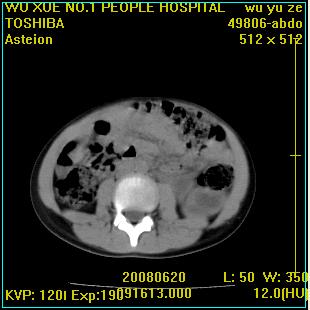

标题: PED0851:患儿,7岁,左腰部外伤一天,伴大量肉眼血尿。 [打印本页]

标题: PED0851:患儿,7岁,左腰部外伤一天,伴大量肉眼血尿。

左输尿管上段梗阻伴左肾盂肾盏扩张积液

左肾积液,输尿管近端扩张,考虑输尿管中下段梗阻  ,左肾结核?

左侧输尿管中段狭窄伴输尿管肾积水,考虑先天性狭窄可能性大.

左肾重度积水,原因不明;不排除左输尿管上段迷走血压迫或先天性狭窄所致可能。

左肾积水,输尿管上段扩张.考虑左输尿管下段狭窄受阻.

左肾积水,左侧输尿管上段扩张。